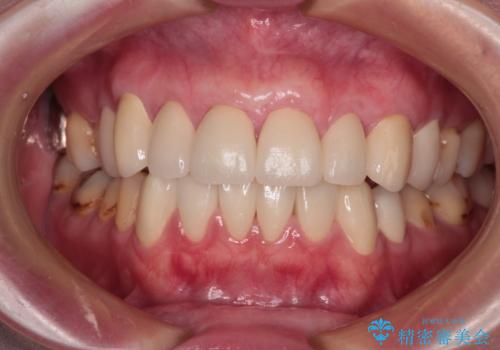

- 他院で矯正治療を終えた結果、下顎前歯の歯肉が退縮してしまい、歯根が見えていることが気になるとのことで来院された患者様です。

歯肉退縮に対して、上顎からの結合組織移植術(CTG)により、歯根の被覆を行うとともに、歯肉の厚みを増すことで将来の退縮リスクを抑制することとしました。

一度の処置で十分に根面被覆ができました。

舌側に歯石が溜まりやすく、やや出血が認められるため、定期的なクリーニングが大切となってきます。